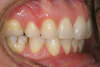

Décalage traité par gouttières

Début de traitement